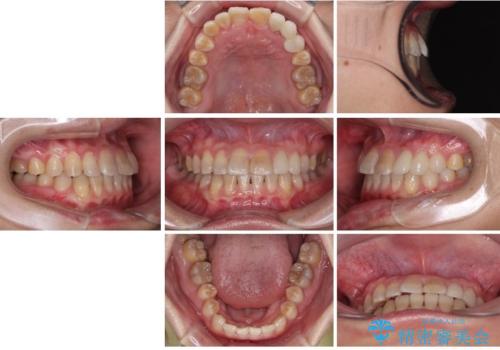

上顎が側方に拡大されて歯が並ぶスペースを確保できました。

それに伴い下顎の歯列も拡大され、舌側に倒れているのが改善されました。